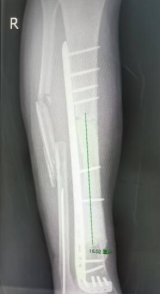

2025年12月,周翔再次到江门市中心医院指导这场关键手术。手术当天,医护团队按照术前规划,有条不紊地开展操作:小心翼翼地掀起之前移植的皮瓣,避免损伤吻合的血管;取出临时填充的骨水泥和固定钢板;在胫骨远近端进行精准截骨,一次顺利完成并在可控制范围之内;随后,将定制好的3D打印金属假体精准植入,调整位置后用螺丝固定牢固。

与之前的手术不同,这场私人定制式的假体植入手术仅用了不到2小时就顺利完成。“术前我们做了充分的规划,假体的尺寸、形态都完全贴合患者的骨骼,所以术中操作非常顺利,没有出现任何意外。”陈元庄介绍,由于术前准备充分,手术创伤也远远小于传统方案,大大减轻了吴大爷的痛苦。

△3D打印定制式胫骨金属假体(可拆分)。